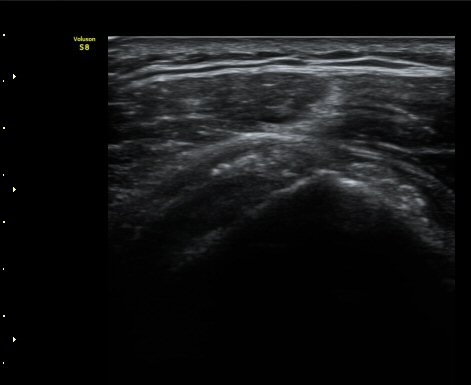

ÆÄ¿öµµÇ÷¯°Ë»ç¿¡¼­ ±Ø»ó°Ç°ú Á¡¾×³¶ÁÖÀ§¿¡¼­ ¼ö¾×Àú·ù°¡ °üÂûµÈ´Ù(±×¸² 6, 7).